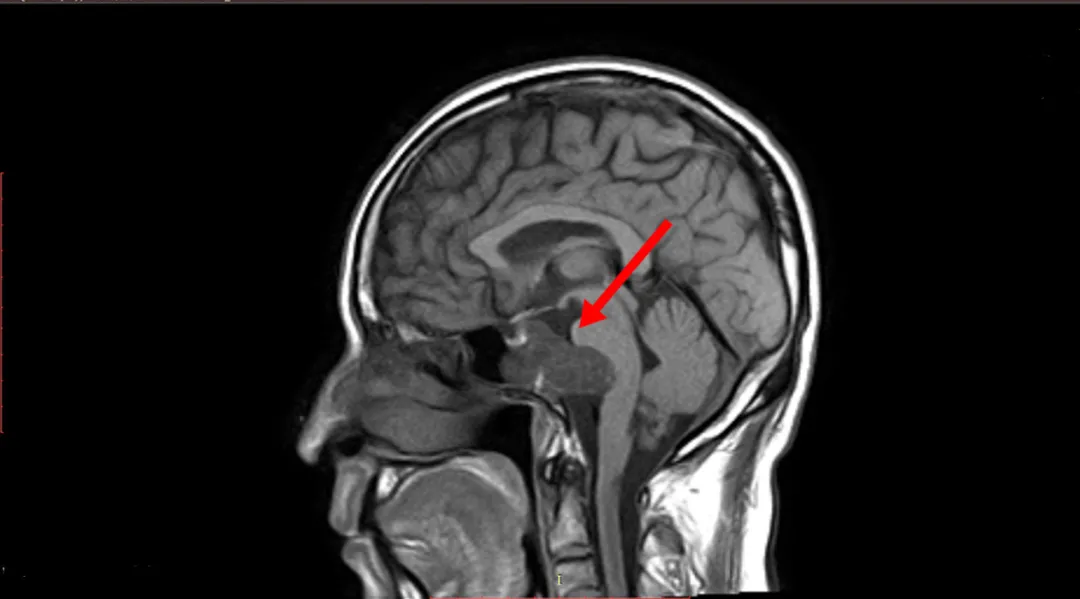

比如下图

![]()

颅底脊索瘤位置深,容易侵犯颅脑及重要神经血管,骶骨脊索瘤如果浸润性生长,会破坏骶骨骨质。